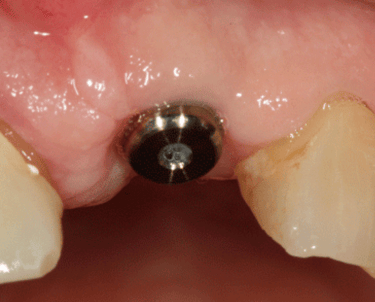

Consiste en insertar un tornillo de titanio en el hueso de la mandíbula o el maxilar, que actúa como raíz del diente y sirve de soporte para una corona, puente o prótesis dental.

Consiste en exponer los implantes después de su integración ósea y colocar los pilares que servirán de soporte para las prótesis definitivas.

Cirugía de Conexión de implantes

Colocación de un pilar provisional para mantener el espacio y la estética mientras se espera la fabricación de la prótesis definitiva.

Colocación de Pilar de Cicatrización